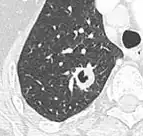

Low attenuating nodule (in this case a fat containing hamartoma).[9] Cavitation with relatively thick wall, in this case aspergilloma).[9]

Cavitation with relatively thick wall, in this case aspergilloma).[9]